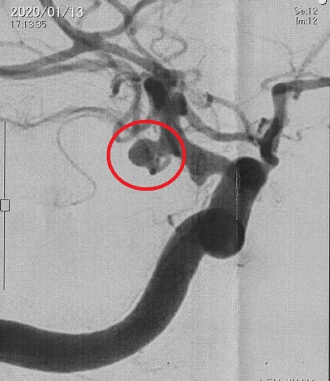

2020年01月18日(土) くも膜下出血の患者さん 当番医の時に頭痛で受診したくも膜下出血の患者さんの報告書が、紹介先の病院から届きました。 脳動脈瘤の破裂が原因で、血管内手術を行って治療したようです。経過は順調であり安堵しました。 この患者さんは、急な頭痛で近くの内科で処方された痛み止めが効かなかったようです。 このように、急に起きた頭痛、痛み止めが効かない頭痛は要注意です。 左写真は頭部MRI検査で、赤丸がくも膜下出血の部位です。 右写真は脳血管造影検査で、赤丸が脳動脈瘤です。